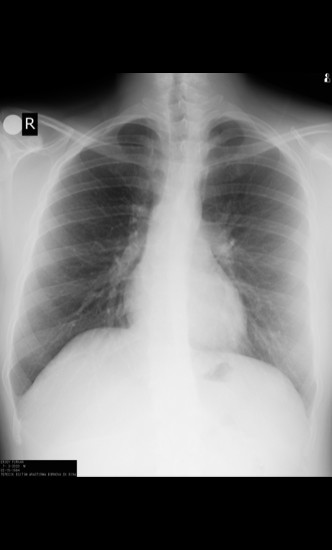

az önce suriyeli radyoloji merkezinde çektirmiş olduğum film. tek türkçe konuşan bendim.